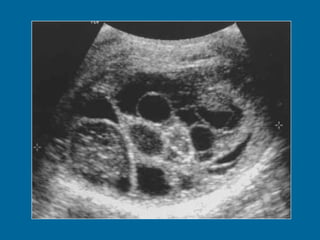

Mature teratoma in a 22-year-old man.  (a) Longitudinal US image of the right testis shows a multilocular cystic mass. The cysts vary in appearance from anechoic to echogenic.

Mature teratoma ina 22-year-old man. (a) Longitudinal US image of the right testis shows a multilocular cystic mass. The cysts vary in appearance from anechoic to echogenic.